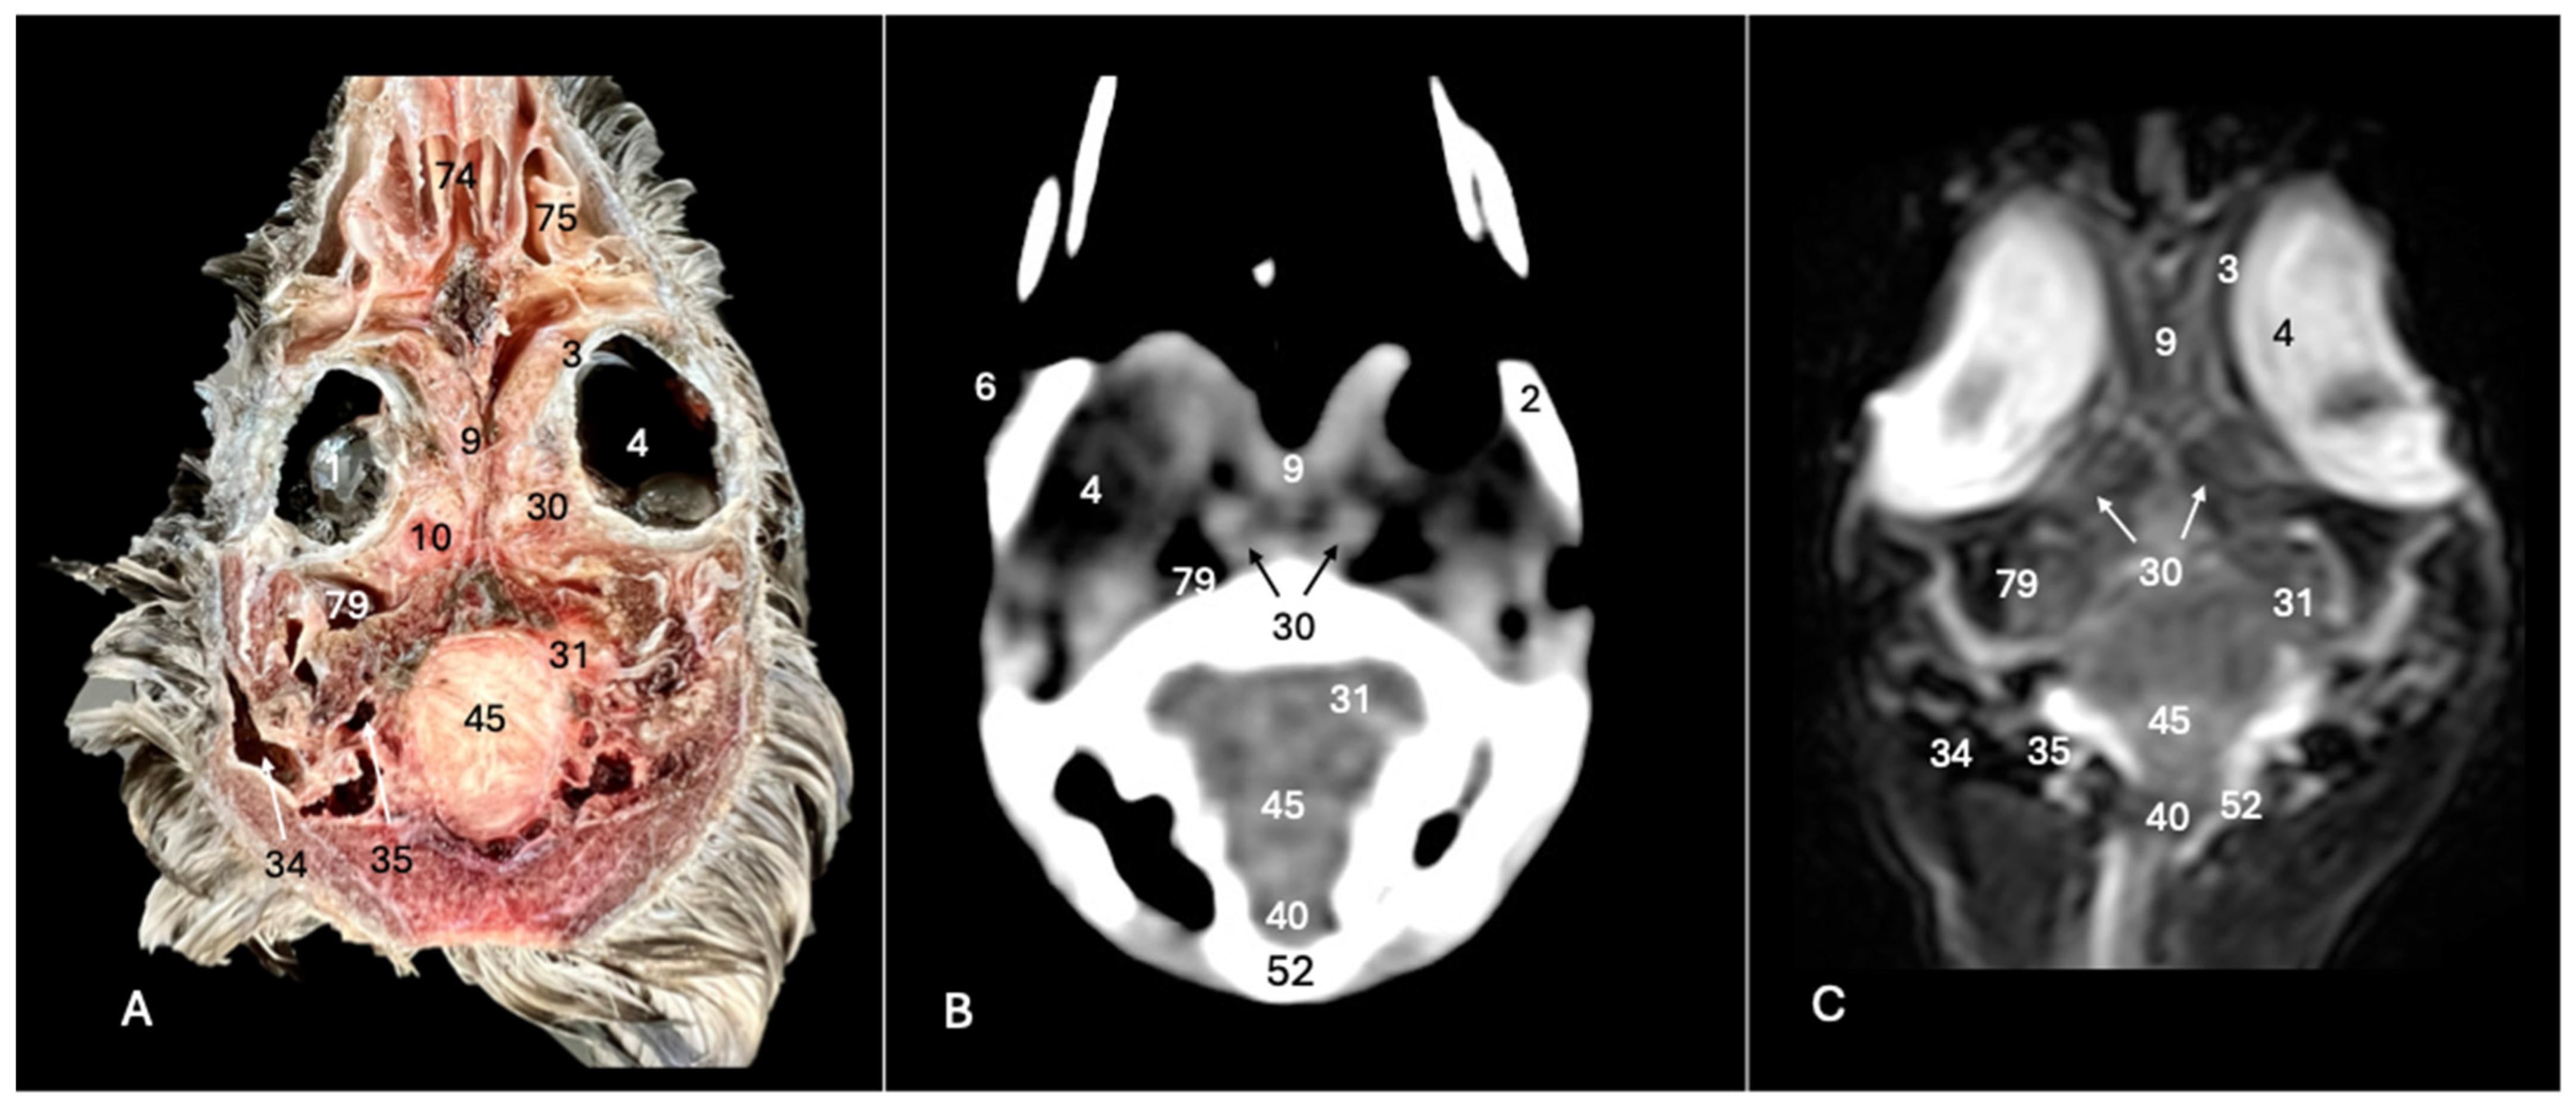

Cory’s Shearwater (Calonectris borealis): Exploring Normal Head Anatomy through Cross-Sectional Anatomy, Computed Tomography and Magnetic Resonance Imaging

3. Result

3.1. Anatomical Sections

3.2. Computed Tomography (CT)

3.3. Magnetic Resonance Imaging (MRI)